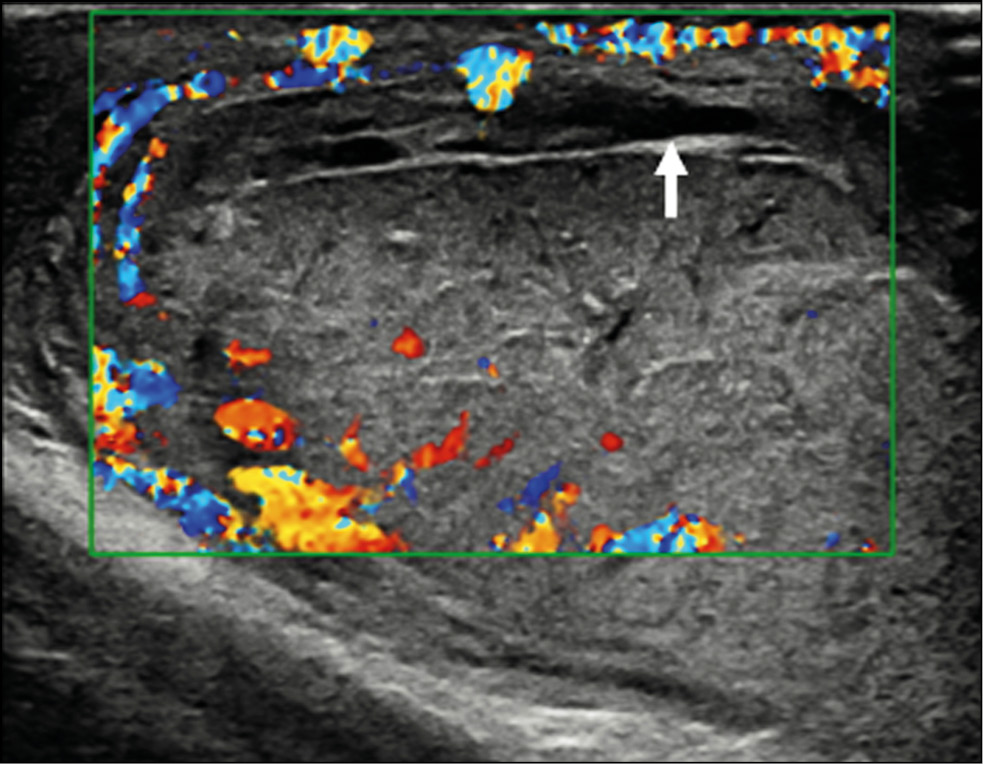

A healthy 15-year-old male teen was hit in the scrotum with a kick in the groin during a football match. He had an immediate and severe pain. After a few hours, although symptoms had improved, he presented to our emergency department with persistent swelling and purplish discoloration of the left scrotum. He did not report any other injuries. The genitourinary examination revealed that the left hemiscrotum was about two times larger than the right with severe ecchymosis. The left testicle was difficult to palpate because of pain and swelling, whereas the right testicle had a normal size and did not reveal any palpable abnormalities. The cremasteric reflex was not elicited on the left side. Scrotal ultrasonography (US) showed moderate scrotal edema and hematocele with a discontinuity in the tunica albuginea characterized by an abnormal contour (Figure 1). Color Doppler US (CDUS) documented a loss of vascularization in the upper pole that extruded into the broken portion of the testicle of approximately 2.5 cm (Figure 2) but no evidence of torsion or infarction. Urology consultation was requested, and a contrast-enhanced US (CEUS) was performed, which confirmed the diagnosis of testicular rupture and determined the amount of the vital parenchyma (Figure 3). The patient was hospitalized for urgent examination of the left hemiscotum based on the US results. During surgery, a large hematocele was evacuated, and a closer inspection of the testicle revealed a lesion of the tunica albuginea. Primary closure of the tunica was performed (Figure 4). The patient made an uneventful recovery, and he was discharged after 4 days.

Figure 2. Color Doppler ultrasonography image showing an irregular testicular morphology with an avascular area at the breaking point (arrow).